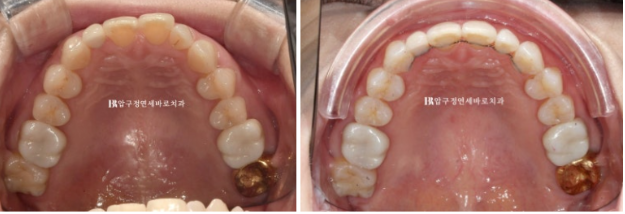

24.02

혀쪽으로 쓰러진 두번째 큰 어금니가 보입니다.

이 때문에 대합치인 위 두번째 큰 어금니와 제대로 교합이 안 되어서 가위교합 상태입니다.

이렇게 엇갈려서 교합이 안되는 상태를 가위교합 이라고 합니다.

치료 전 후 보겠습니다.

좌 - 치료 전 / 우 - 치료 후

앞니 배열 개선과 가위교합 개선

쓰러진 큰 어금니는 잘 세웠습니다.

치간삭제를 통한 아래 앞니 배열의 개선